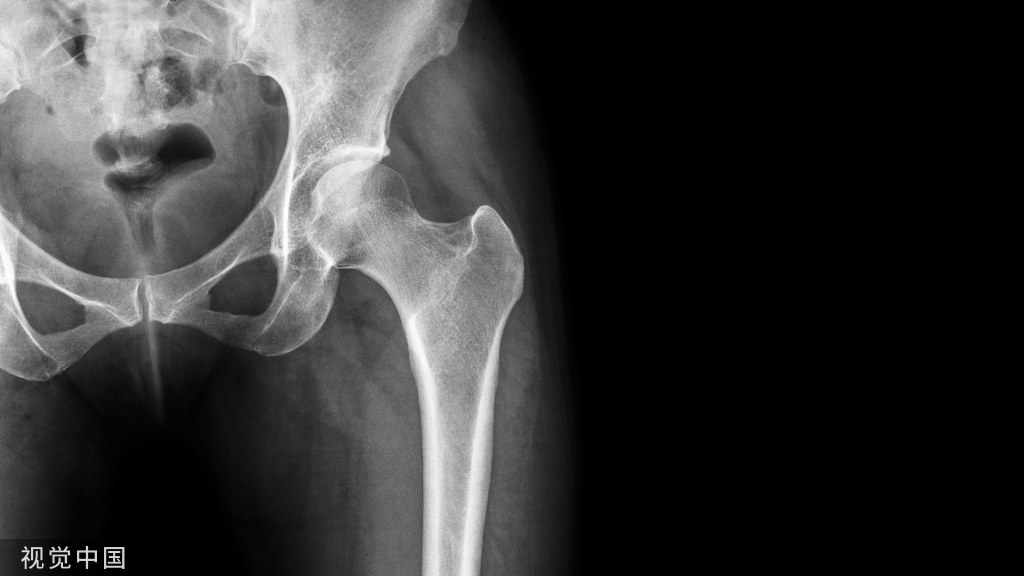

二、国产骨科内固定装置1. 优点(1)价格适中:国产骨科内固定装置的价格相对较低,减轻了患者的经济负担。(2)适应症广泛:国产骨科内固定装置适用于多种类型的骨折,为患者提供了更多的选择。(3)国产化程度高:国产骨科内固定装置的国产化程度较高,在某些方面不比进口的产品差,同时有利于降低采购成本和维护成本,医保报销比例大也是国产产品的优势。

2. 缺点(1)技术水平有待提高:与进口产品相比,国产骨科内固定装置在技术水平和设计方面可能存在一定的差距。(2)质量参差不齐:由于国内市场存在多个品牌和生产厂家,因此国产骨科内固定装置的质量可能存在差异。